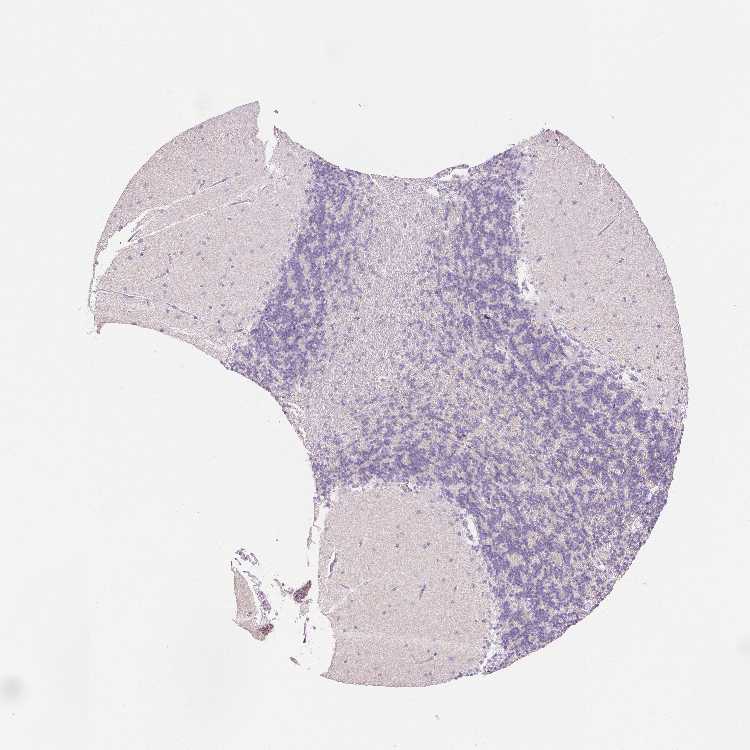

CEREBELLUM - Antibody stainingi

Antibody staining in the annotated cell types in the current human tissue is reported as not detected, low, medium, or high, based on conventional immunohistochemistry profiling in selected tissues. This score is based on the combination of the staining intensity and fraction of stained cells.

Each image is clickable and will lead to virtual microscopy that enables deeper exploration of all samples and also displays staining intensity scores, fraction scores and subcellular localization as well as patient and tissue information for each sample.

Antibody HPA034504Antibody HPA034505

Purkinje cells Not detectedNot detected

Cells in granular layer Not detectedNot detected

Cells in molecular layer Not detectedNot detected